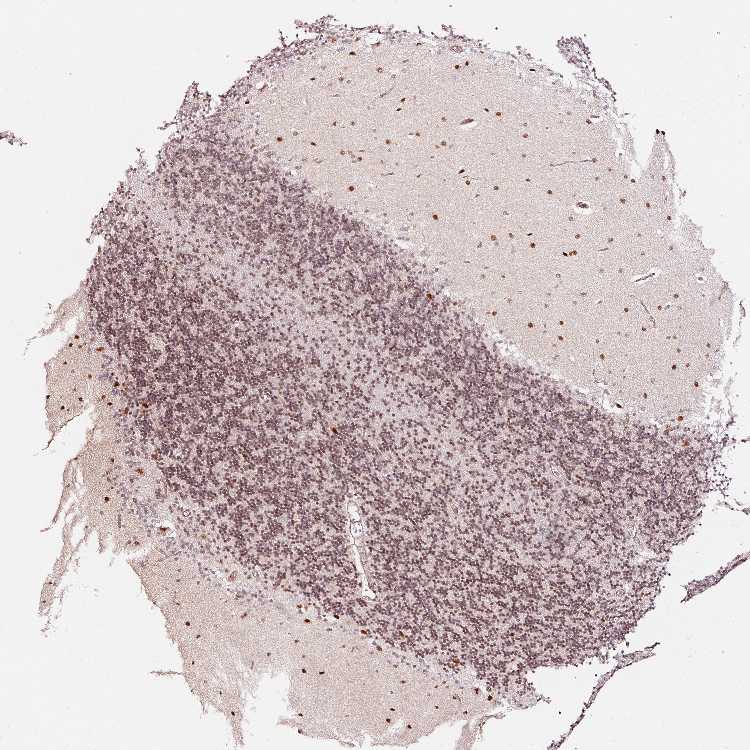

CEREBELLUM - Antibody stainingi

Antibody staining in the annotated cell types in the current human tissue is reported as not detected, low, medium, or high, based on conventional immunohistochemistry profiling in selected tissues. This score is based on the combination of the staining intensity and fraction of stained cells.

Each image is clickable and will lead to virtual microscopy that enables deeper exploration of all samples and also displays staining intensity scores, fraction scores and subcellular localization as well as patient and tissue information for each sample.

Antibody HPA047089Antibody HPA053624

Purkinje cells LowMedium

Cells in granular layer MediumMedium

Cells in molecular layer MediumHigh